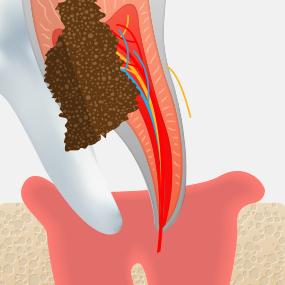

충치가 어느 정도 진행되었는지에 따라 치료 방법은 크게 달라질 수 있습니다. 서울하나치과는 정밀 진단을 통해 치아를 최대한 보존할 수 있는 치료법을 안내해드립니다.

CARIES TREATMENT

치아 내부에 있는

조직이 괴사되고,

뿌리 주변의

염증으로 인하여

뼈가 점차 소실됩니다.

신경조직이 감염되거나 오염된 경우에는 신경치료가 필요합니다. 서울하나치과는 우수한 재료와 체계적인 치료 과정을 적용하여 안정적이고 높은 성공률의 신경치료를 제공합니다.